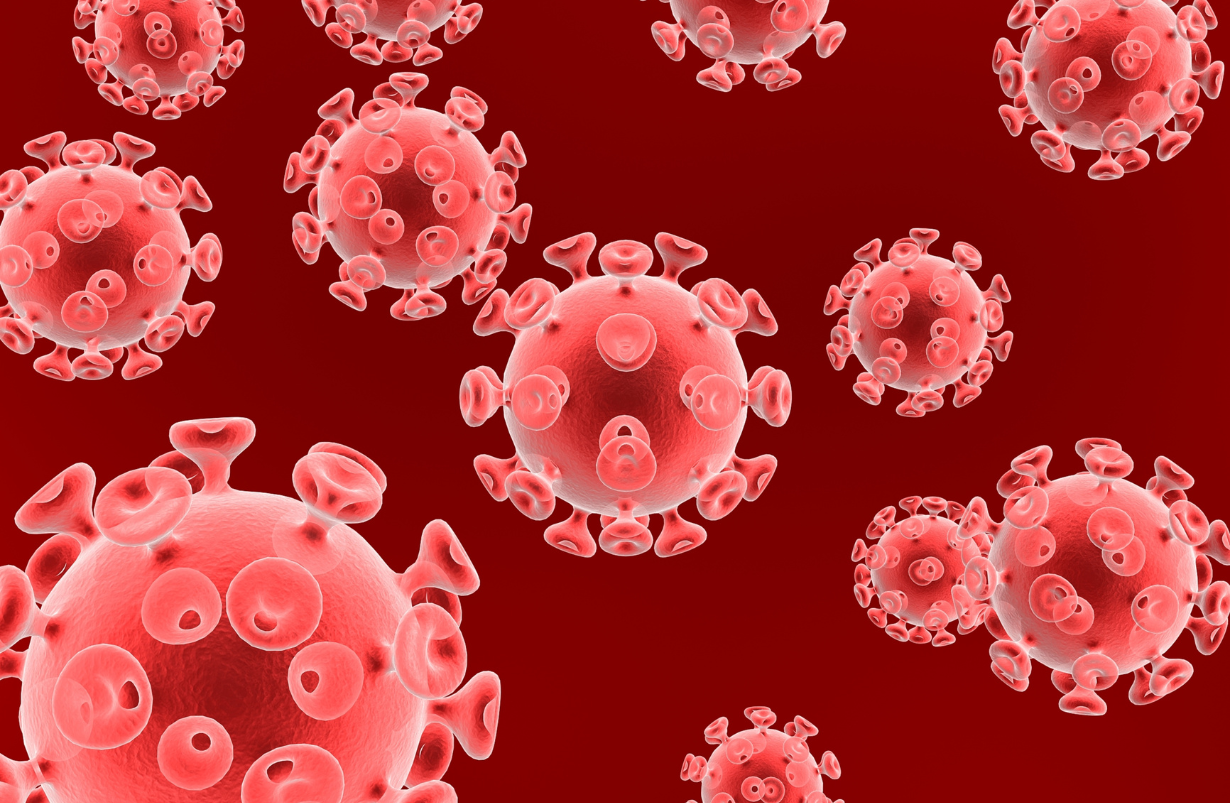

COVID-19

3/22/2020: A novel respiratory virus in the coronavirus family that became a pandemic in 2019-2020. Its cardinal symptoms are high fever, dry cough and shortness of breath, the latter being present approximately 20% of the time. Effective breathing can become so impaired that a respirator is necessary. Mortality is in the 1-4% range, with elderly and debilitated persons being particularly at risk. The Chinese experience suggests that people at 80 years or more have a 15% mortality rate, while people under 40 years of age have mortality of 0.2%. Further breakdown approximates further liabilities regardless of age: Cardiovascular = 10%; Diabetes Melletis = 7%; Chronic Respiratory Conditions = 6%; Hypertension = 6%; Cancer = 5.5%, while those with no health-related condition have a 1% mortality. During the pandemic, regions of high incidence are advised to practice "Sheltering in Place," which entails going out of one's home and encountering others as seldom as possible, keeping a "social distance" of 6 feet or more, and closing of non-essential businesses and all entertainment and cultural activities Pharmacies, groceries, and health facilities remain open. Transportation is mnimized. Although no cure is known at this writing, Chloroquine and Hydrochloroquine (medicines used in Malaria, and for Lupus Erythematosis and Rheumatoid Arthritis), were in current clinical trials (https://www.covidtrial.io/), and other medications such as the antibiotic Azithromycin (Z-Pack) and Ramdesivir, (a medication used vs. Ebola), the best clinical trial coming out of China, and Lopinavir/Ritonavir, with a mildly positive report in the New England Journal of Medicine on March 18, 2020 (Circa199-patient controlled study found 1 day shorter recovery in severely affected individuals, with more gastrointestinal but less overall complications in the treatment group. B,Wang Y, M.D., Wen D, Liu W, Wang J, Fan G, Ruan L, Song B, Cai Y, Wei M, Li, X M.D., Xia J, M.D., et al. A Trial of Lopinavir–Ritonavir in Adults Hospitalized with Severe Covid-19. DOI: 10.1056/NEJMoa2001282). A study at the University of Nebraska is evaluating Ibuprofen. Nutritional remedies include Zinc, 12 mg/day, an element plentiful in oysters, and also present in elderberry, beef, breads and legumes, and Selenium, 100 -2-- mcg/day, which is found in Brazil nuts, seafoods and also in breads. Since weakness in respiratory muscles and lowered immunity are prominent in COVID-19, yoga has significant benefit in raising the strength of respiratory muscles, oxygenating little-used lung fields, and lowering anxiety, a major source of lower immunity. Contraindicated is an arduous workout, since strenuous activity is known to impair immunity in the short run. When no contagion is threatening, reasonably challenging yoga series are highly recommended. Breathing exercises to strengthen and coordinate respiratory musculature, and raise tidal volume, and for calm, are highly recommended. Visama Vritti Pranayama and Viloma Pranayama are particularly useful in raising your general pulmonary health, as a preventative measure. For Viloma see the video in Insomnia. .